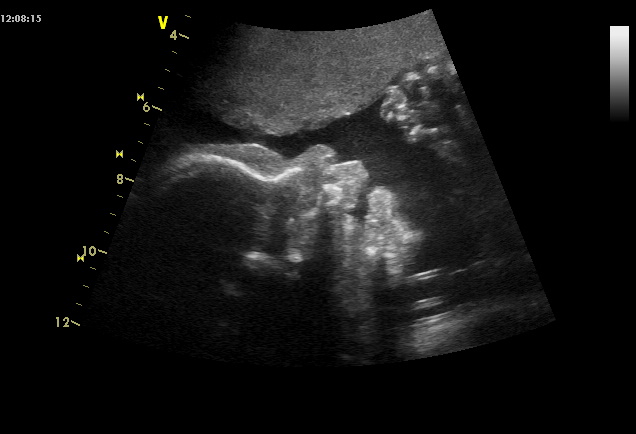

Dnes na kontrole vše v pořádku, opět mi udělala doktrorka rychlý UZ, malej snad poprvé spinkal, ruce před obličejem. Řekla mi, ať už zas beru jen jedno magnézko denně, pokud je to klidné, abych prý neměla průjem. To mi teda asi nehrozí

. Malému naměřila asi 914 g, takže o dost míň než včera doktor (990). Aspoň vidíte, že je to jen orientační měření, plus mínus autobus

A tady jsou některé fotky ze screeningů